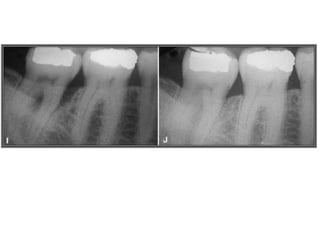

TRATAMENTO DAS LESÕES

ENDOPERIODONTAIS

Hemisseccção

DEL RIO, 1996